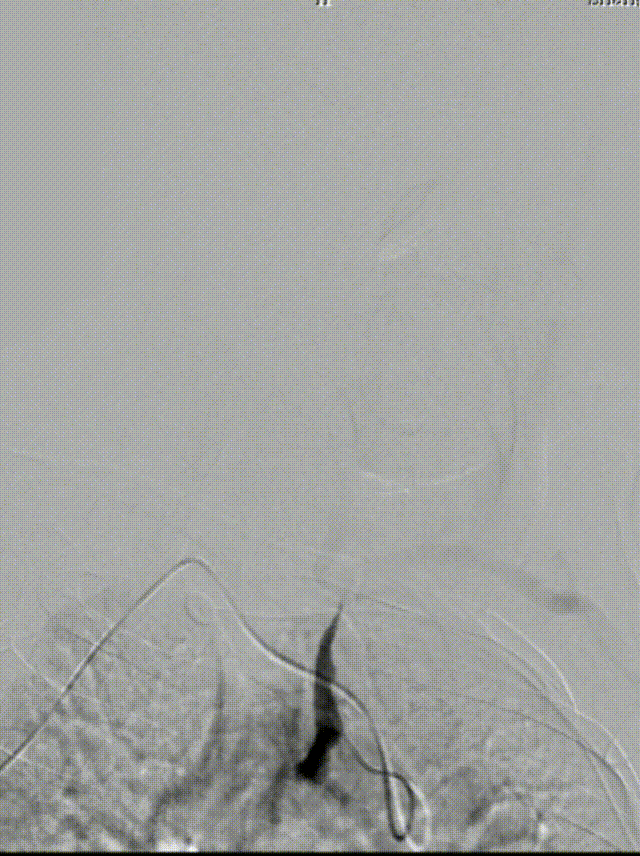

DSA:LSub。

0.018*300cm 外周导丝至左肱动脉,0.014*200cm 通桥北斗SS™神经血管导丝超选至左椎V2段远端。

沿0.018*300cm 外周导丝送入6*40 外周球囊送至左侧锁骨下动脉狭窄处,压力泵逐渐加压到6atm。

撤出球囊后见残余狭窄40%。

再次沿0.018*300cm 外周导丝送入6*40 外周球囊达LSub狭窄部位,压力泵逐渐加压到8atm,见残余狭窄20%。